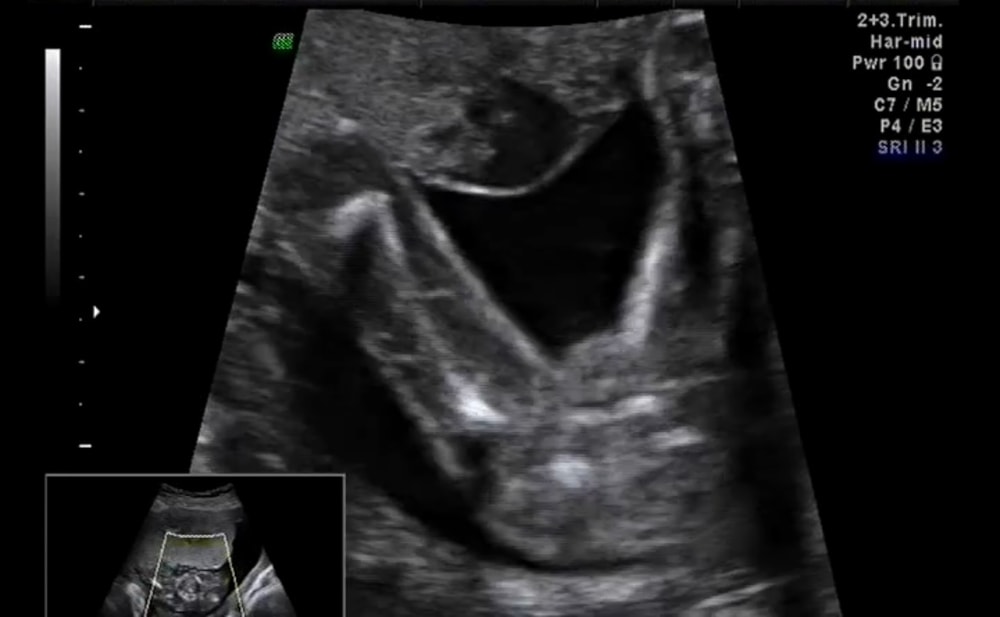

Мальчик в 16 недель Ракурс снизу вверх между ножек Изображение